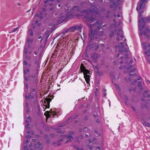

being deposited distally as the hair is plucked {194}. Pigment casts are due to injury to the hair matrix, although some authors have theorized that they result from the sudden conversion of anagen to catagen . Hair shaft changes, termed trichomalacia, may be seen. Characterized by diminished size, distorted and odd shape, and irregular pigmentation of the shaft, trichomalacia is additional evidence of trauma to the matrix . Traumatized follicles can also show considerable distortion of the bulbar epithelium and conspicuous hemorrhage . |

Pigment casts, which are clumps of melanin pigment, may be seen in the hair papilla and peribulbar connective tissue. They are also commonly seen in the upper portion of the hair follicle as a result of pigmented matrical cells |

Histopathology. In horizontally sectioned biopsies of trichotillomania uncomplicated by the coexistence of other types of alopecia, the density of hair follicles is normal, as is the terminal-to-vellus hair ratio. The diagnostic finding, when seen, is distorted hair follicle anatomy, without inflammation . Specifically, the pulling of hairs can leave behind empty anagen follicles and "torn-away" follicles, the result of plucked hair shafts that retain parts of the hair matrix and root sheaths . Additional microscopic evidence of traumatic injury was published by Royer et al. as the "hamburger sign," describing a vertically oriented split in the hair shaft containing proteinaceous material and erythrocytes, resembling a hamburger within a bun . Damaged follicles enter the resting phase, leading to an increase in the percentage of catagen and telogen hairs, as high as 75% . Often the hairs do not become normal catagen hairs and appear distorted and abnormal . |